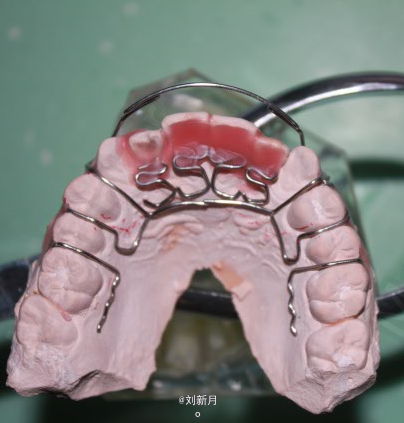

诊断:安氏III类错合 矫治计划 1.前期活动矫治,后期MBT矫治技术 2.非拔牙矫治 3.利用低位唇弓解除反合,后期排齐整平牙列 4.矫治结束后尖牙,磨牙,覆合覆盖基本正常 5.面型有所改善